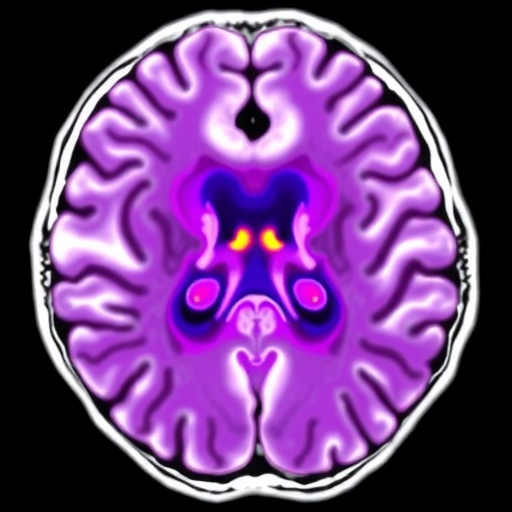

In a groundbreaking study published in the 2025 edition of BMC Psychiatry, researchers have unveiled compelling evidence linking non-alcoholic fatty liver disease (NAFLD) to disruptions in the brain’s glymphatic system, a vital network responsible for waste clearance and overall neurological health. Utilizing an advanced magnetic resonance imaging (MRI) technique, diffusion tensor imaging along the perivascular space (DTI-ALPS), the team explored how pre-cirrhotic NAFLD patients experience significant alterations that may contribute to cognitive decline.

In this cross-sectional analysis, 43 male patients diagnosed with pre-cirrhotic NAFLD, averaging 38 years of age, were compared with 23 controls matched for age, sex, and education. Both groups underwent rigorous cognitive assessments alongside specialized diffusion tensor imaging to calculate the ALPS index—a quantitative measure reflecting glymphatic function by evaluating water diffusivity along perivascular spaces.

Results from the study highlighted a marked reduction in the ALPS index within the NAFLD cohort relative to their healthy counterparts, even after controlling for confounding factors such as age, sex, and body mass index (BMI). This decline suggests an impaired clearance mechanism within the brain’s glymphatic system, potentially exposing neural tissue to buildup of harmful substances and toxins.

Further analysis revealed increased diffusivity along projection fibers in the direction of the y-axis among NAFLD patients—a finding indicative of microstructural abnormalities possibly linked to neuroinflammation or subtle white matter damage. These changes were robust, underscoring that NAFLD’s impact may extend beyond the liver, influencing neurological integrity at a microstructural level.

Correlations drawn between the ALPS index and cognitive performance reinforced the clinical significance of the findings. Notably, lower ALPS values were associated with poorer scores on the Mini-Mental State Examination (MMSE) and the clock drawing test, two widely recognized metrics for evaluating global cognition and executive function. This association hints at a potential mechanistic link between glymphatic dysfunction and the early cognitive deficits observed in NAFLD patients.